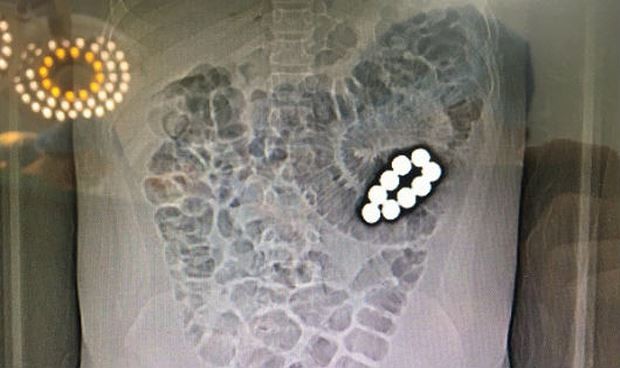

Về sự việc trên, chiều 24.9 thông tin từ BV Quận Thủ Đức cho biết, sáng 22.9, bệnh nhi L. được người nhà đưa đến Khoa Cấp cứu BV quận Thủ Đức do đau bụng nhiều, bụng chướng và nôn ói. Sau khi khám, chụp Xquang, siêu âm và CT MRI…, các bác sĩ chẩn đoán bệnh nhi bị tắc ruột do dị vật, cần chuyển mổ cấp cứu gấp.

Trong khi tiến hành can thiệp mổ, bác sĩ phát hiện bệnh nhân bị tắc ruột do 9 viên bi nam châm bằng sắt nằm ở 2 khoang ruột khác nhau. Một khoang chứa 7 viên và khoang còn lại chứa 2 viên. Hai nhóm viên bi bị nam châm hút 2 đoạn ruột lại với nhau gây tắc ruột hoàn toàn và gây hoại tử ruột.

Các bác sĩ BV quận Thủ Đức phải tiến hành cắt một đoạn ruột để lấy 9 viên bi ra, loại bỏ phần ruột bị hoạt tử và khâu nối lại ruột. Sau 3 giờ căng thẳng, ca phẫu thuật đã thành công tốt đẹp.